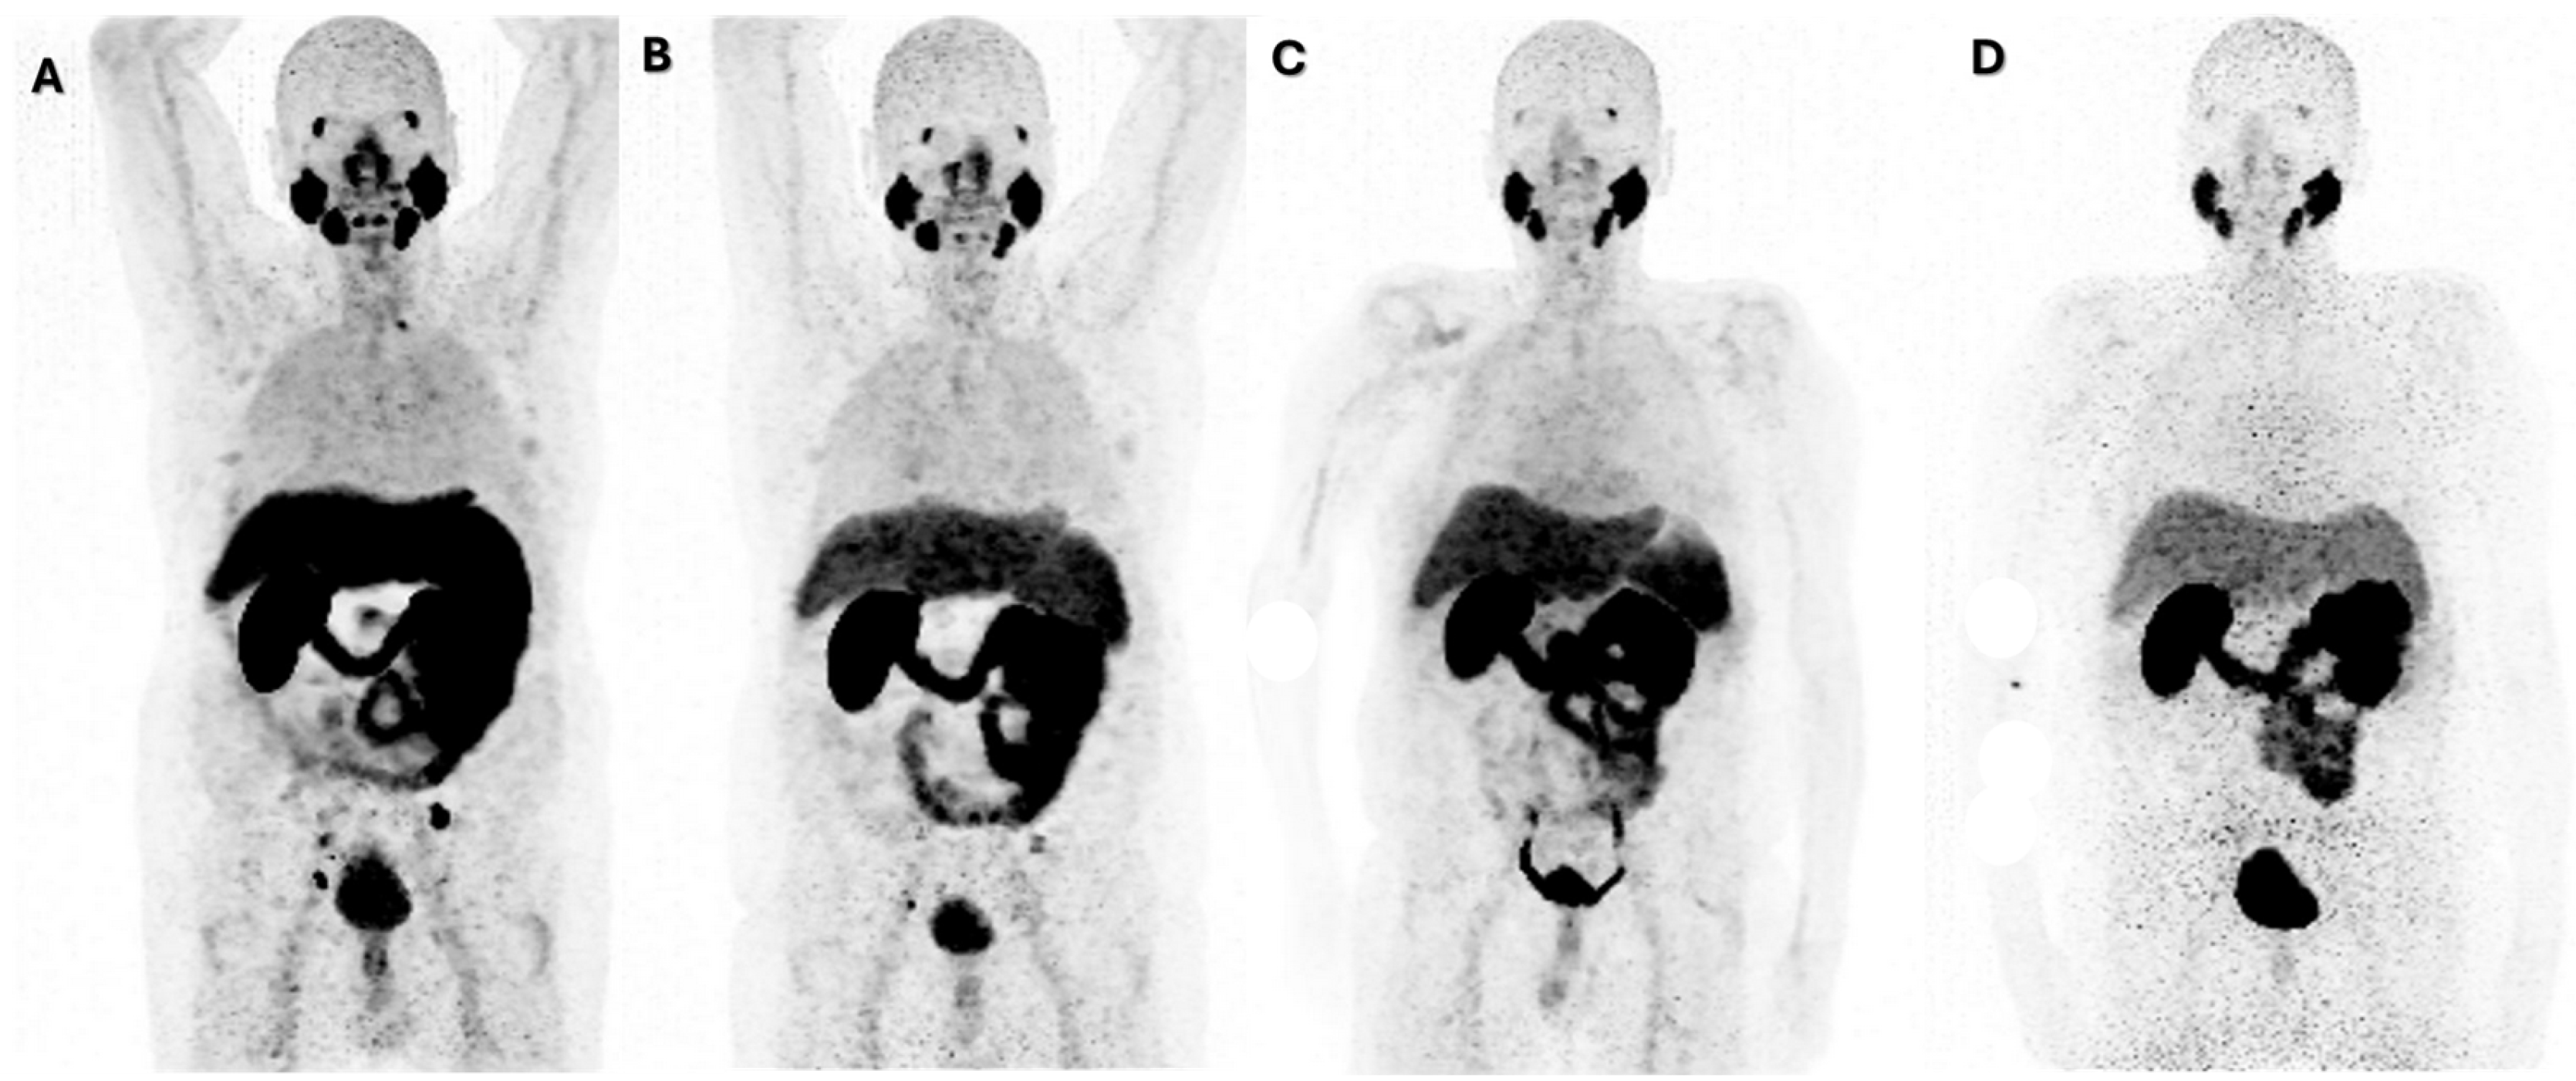

3. Results

| Goserelin, Enzalutamide | 10Plasmacytoid variant MSI-H/PDL1 | LNM, Prostate, Locally advanced in bowel and bladder | 4 | 48 | 100 |